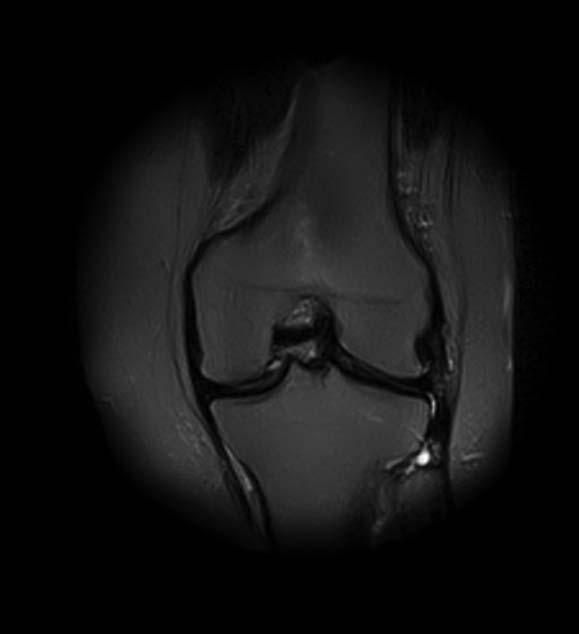

1. травма 5 лет назад - "ударилась коленом", с тех пор боли в суставе

3. стандартные рентгенограммы с небольшими изменениями - сужение медиальной суставной щели

5. сустав клинически стабилен

|